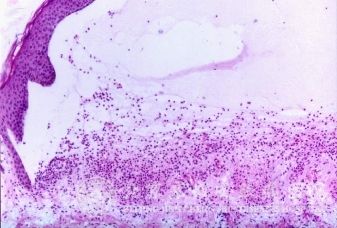

北京京城皮肤医院指出,药敏性皮炎的发病机理:发病机理主要为变态反应:大多数的药疹都由变态反应引起,与药疹有关的变态反应有Ⅰ型变态反应、Ⅱ型变态反应、Ⅲ型变态反应、Ⅳ型变态反应。